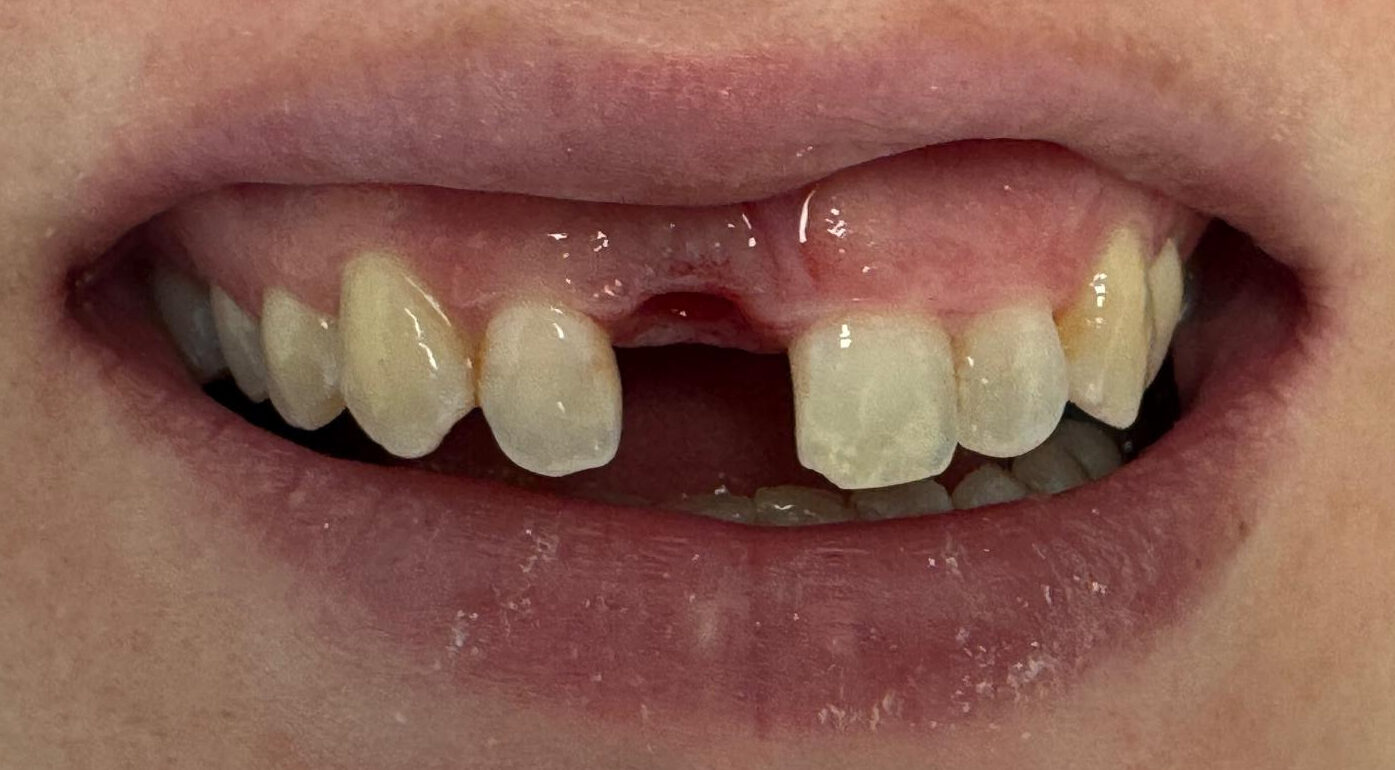

Incisor Implant

Missing front incisor

Before

After